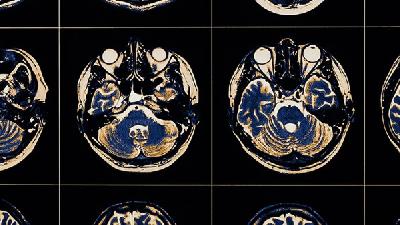

“脑细胞介入修复疗法”是一种中枢神经再生疗法,能短时间内修复患儿受损脑细胞,恢复脑部病灶供血供氧,激活受损“休眠”脑组织细胞,促进脑细胞新生。